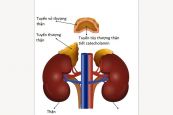

Lao đường tiết niệu sinh dục là bệnh của hệ thống tiết niệu sinh dục, bao gồm đường tiết niệu và hệ thống sinh sản. Đây là dạng nhiễm trùng lao ngoài phổi. Vậy nguyên nhân và triệu chứng của bệnh là gì? Phương pháp điều trị và phòng ngừa nào là hiệu quả? Tham khảo ngay bài viết dưới đây để hiểu rõ hơn nhé!

Xét nghiệm kích thích hormone vỏ thượng thận (ACTH) với cosyntropiních giúp biết được vỏ tuyến thượng thận của bạn hoạt động có tốt hay không. Vậy xét nghiệm này bao gồm những gì? Kết quả của xét nghiệm được đọc như thế nào? Mời các bạn tham khảo bài viết dưới đây để hiểu rõ hơn nhé!